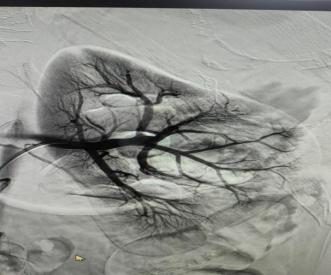

术中通过DSA造影,顺利找到肾脏出血的精准位置,左肾平滑肌脂肪瘤供血动脉破裂出血。通过微导管超选出血责任血管并栓塞出血动脉,有效地阻止了出血。在完成栓塞后,对原出血部位进行了再次的造影检查,发现原本外溢的造影剂已经消失,这表明出血动脉已经被成功封堵。术后患者生命体征平稳,症状较前明显改善,尿液由血红色逐渐恢复清亮。